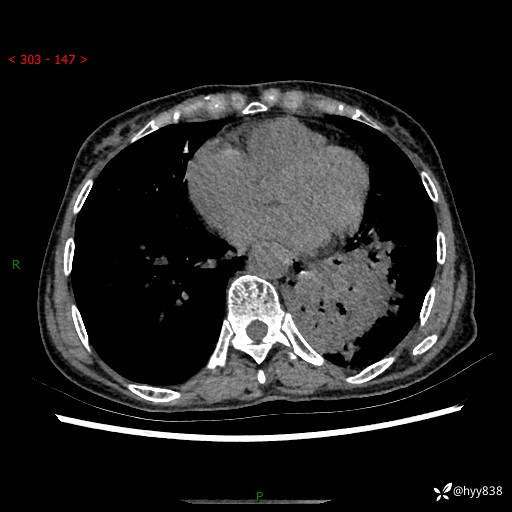

胸部CT平扫+增强